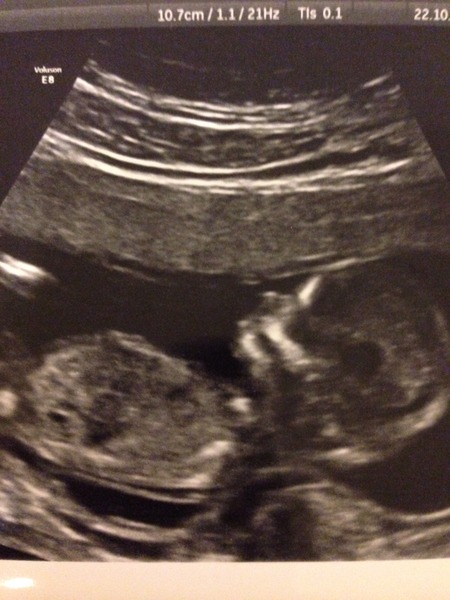

Kitty beautiful, clear scan pictures! Congratulations!

Loving the really clear scan pic GettheRed!! Definitely stay on this bus if you want to, chances are will be a May birth anyway Grin

WigglyWigglyWoo Great scan picture - and pleased to hear about your Harmony test results! Congratulations! x

Love these scan pics! The 12 week scan is so exciting (terrifying!)